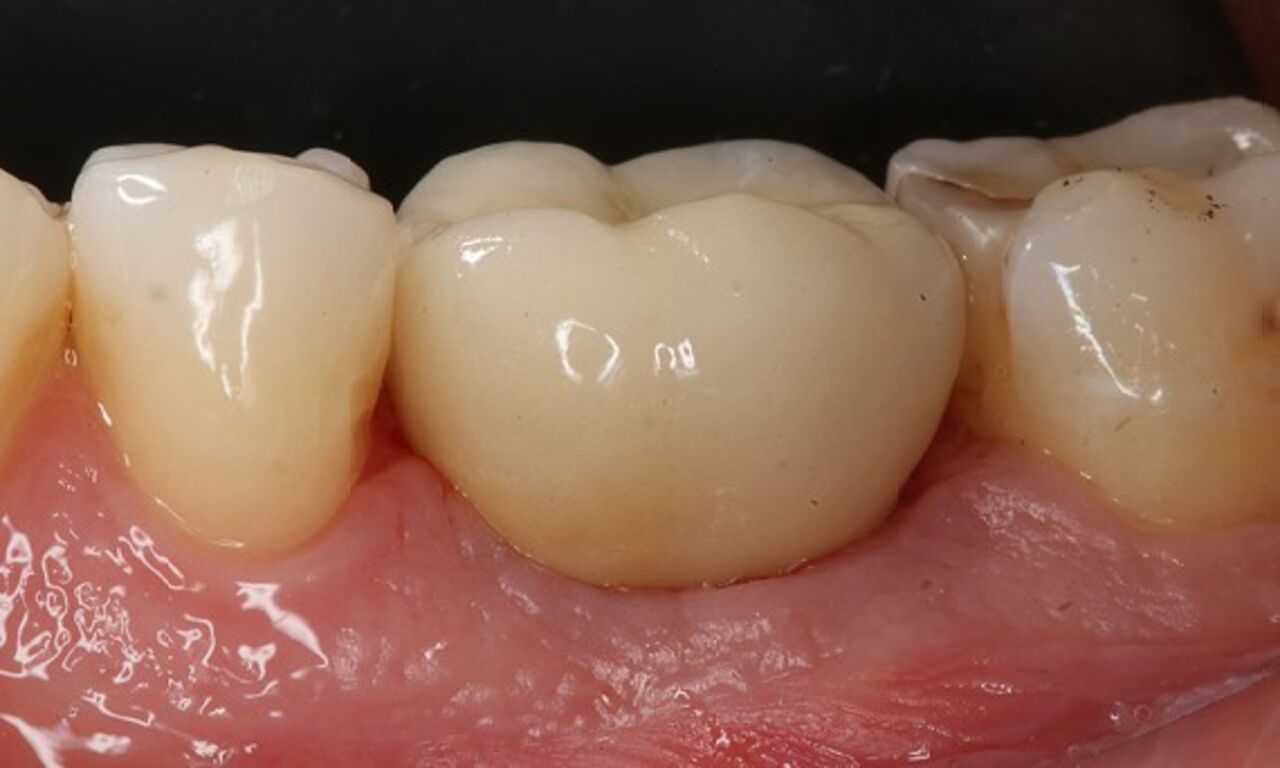

Exzellente Ästhetik

Langfristiger marginaler Knochenerhalt für eine exzellente Ästhetik über Jahre hinweg. Sie wissen, dass Sie gewonnen haben, wenn Ihr anspruchsvollster Patient dauerhaft zufrieden ist.

Langfristiger Knochenerhalt und exzellente Ästhetik dokumentiert und klinisch erprobt.

Die Hauptmerkmale des Implantats – EV-Innenverbindung, OsseoSpeed, MicroThread, Soft Tissue Chamber – wurden für das Astra Tech Implant System hinsichtlich Knochenerhalt und Ästhetik dokumentiert und klinisch erprobt.

SoftTissue Chamber – größeres Weichgewebevolumen und hohe Ästhetik